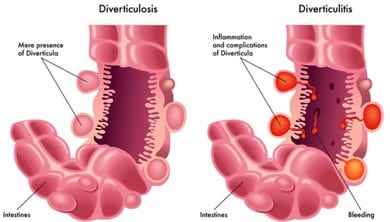

¿Qué onda con la enfermedad diverticular?

Diverticulitis: Es la inflamación o la infección de pequeñas bolsas llamadas diverticulos que se desarrollan a lo largo de las paredes de los intestinos, principalmente en el colon.

O sea, cuando un divertículo se rompe y la infección se establece alrededor del divertículo.

Diverticulosis: Cuando se forman y aparecen estas bolsas. Aparecen a partir de los 45-50 años y aumentan con la edad.

Posibles Causas

Dieta baja en fibra.

Aumento de la presión en el colon.

Debilidad en la pared del colon.

Divertículos: Los divertículos se producen por un aumento de la presión en el interior del tubo, que afecta a paredes musculares, haciendo que se engrosen y, por tanto, reduciendo la luz del intestino.

El tamaño de estos divertículos varía entre los 0,2 y los 2,5 centímetros. Existen casos en los que el paciente presenta un solo divertículo gigante, que varía entre 2,5 y 15 centímetros, pero estos casos son muy raros.